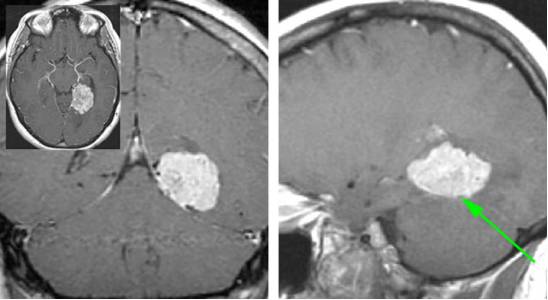

图1. 图示天幕脑膜瘤。术者通过经天幕小脑上入路来避免术中由于暴露不够而对颞叶的切除。

图2. 天幕脑膜瘤。如上图所示病例,肿瘤可以沿天幕表面扩展。在此患者中,后颅窝的占位压迫导致相应症状。此病例分期分别通过乳突后和颞下入路两步来切除。